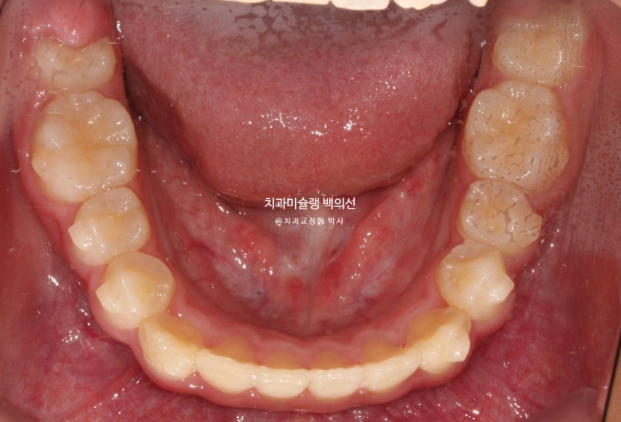

254년 10월부터 25년 1월까지 14개 추가장치를 모두 낀 후 모습입니다.

25.01

추가장치에서 중심선 개선을 위한 고무줄을 처방했는데 아이가 고무줄을 너무 열심히 껴준 덕에 중심선이 오히려 3개월 전에 비해 반대로 넘어간 것이 보입니다.

이런 경우 고무줄을 중단하면 어느정도 원래 위치로 돌아오기 때문에 마지막 꼈던 14단계 장치를 유지용으로 잘때만 끼면서 경과 관찰을 하기로 합니다.

그렇게 4개월간 경과관찰을 하던 중 25년 5월 내원시 모습입니다.